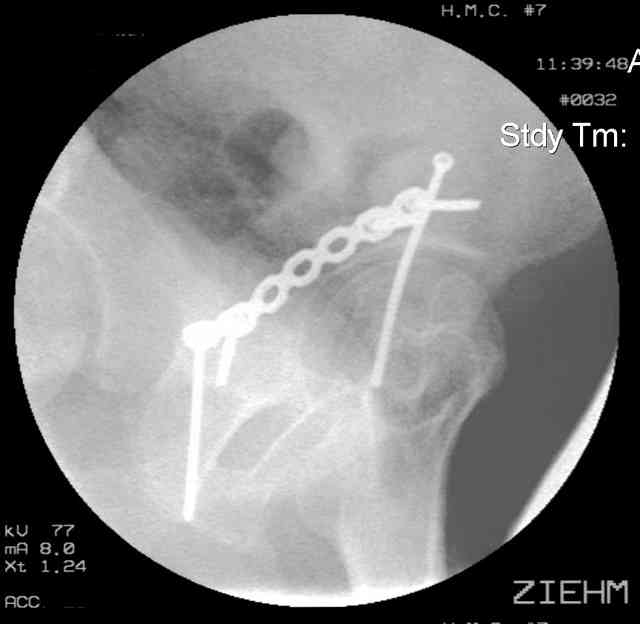

Screw insertion using the obturator-outlet combination image.

12.Prone Obturator-Outlet

Same with a contoured pelvic reconstruction plate applied and tensioned.

Prone Iliac Oblique

The other oblique reveals the extra-articular implants.... you know the AC screw is extra-articular from the other views.

Routine Fixation

AC Screw

PC Neutr Plate

Others

The unstable caudal segment is secured by the lower 2 plate screws and the AC medullary screw... always assure that your fixation is sufficient to defeat the instability... part of your prop plan... but assure it before you close... it¹s your last chance... you shouldn't have to be pushing on the hip in contorted ways to determine your fixation stability...you can if that makes you 'comfortable'.